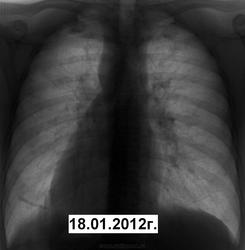

Я так понимаю , что не понравились малоинтенсивные тени в латеральных отделах слева ? Кнаружи от среднеключичной линии ?  В ГТД его родимого !

Вижу именно то, что отметил Фил. Может там ТБС и не будет, и его еще куда отправят, но будет участие. По крайней мере не скажут, что ничего не видел, не внимательно смотрел. Потом это будет всем видно.

Коллега, не обременяйте свой карман лишними тратами, лупа есть рабочем столе ПК. На сайте уже не раз произносилась фраза "глаз зацепился", вот и все. Тем более, что на предыдущей флюшке он, практически, не цеплялся. Вот я и приложил усилия, что бы он зацепился (или отцепился) еще и у коллеги фтизиатра. Есле вдруг вылезет завтра бяка, то, поверьте, даже при отрицательной лупе каждый начинающий укажет мне мою близорукость.

что Игорь Иванович поступил тактически правильно. Больше всего боюсь в таких случаях госпитализации пациентов в туберкулезный стационар. Подобных больных следует быстро обследовать амбулаторно. Возможно, имеется нетуберкулезная патология (саркоидоз?). Не по душе мне и эта тень (см. рисунок). Надеюсь получим сведения об окончательном диагнозе. С уважением Nikolas